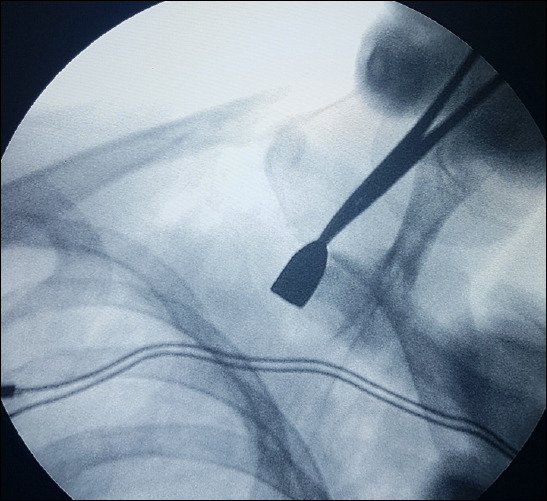

Background: This study aimed to evaluate the epidemiological data on thoracic and abdominal firearm injuries in children treated by pediatric surgeons at a pediatric trauma center.

Methods: Children hospitalized with firearm injuries from 2015 to 2022 were retrospectively analyzed. Patient demographics, affected organs, treatment, and length of hospital stay were analyzed retrospectively.

Results: The mean age of the patients was 12.43+-2.31 years; 27 (84.4%) were male and five (15.6%) were female. Bullet injuries were associated with higher severity and often required major surgical intervention, whereas pellet injuries were generally managed conservatively. For thoracic injuries, conservative management was considered effective for stable cases without immediate life-threatening complications, whereas abdominal injuries more often required invasive surgical approaches. Notably, unintentional firearm injuries were more common in younger children, whereas intentional injuries were more common in older adolescents. This age-related pattern highlights a statistically significant correlation between age and type of firearm injury (p = 0.002). Also, the majority of patients with thoracic injuries underwent minor surgeries, whereas those with abdominal injuries mostly underwent major surgeries Conclusion: Our study indicates that accidental firearm injuries are more common among younger age groups, whereas intentional firearm injuries tend to occur more frequently among older children.